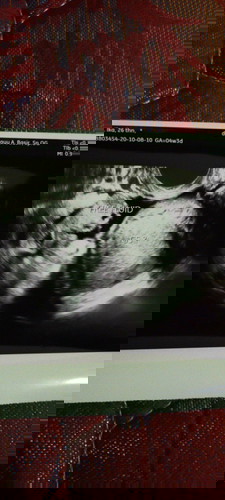

Ada yg samaan gak Bun?, usia kandungan 8w. Jdi kemarin tggl 30 sampai hari ini tanggal 31 aku ngalamin kram perut bagian bawah sbelah kiri. Dan hari ini abis dri puskesmas aku ngeluarin flek.. Itu gimana ya Bun? Tolong bantu share yg punya pengalaman kayak gini....worry soalnya aku kehamilan pertama #bantusharing